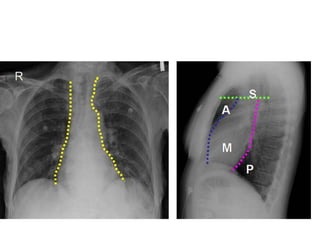

• On the lateral

radiograph

• drawing an imaginary

line anterior to the

trachea and

posteriorly to the

inferior vena cava.

• The middle and

posterior

compartments can be

separated by an

imaginary line passing

1 cm posteriorly to the

anterior border of the

vertebral bodies.